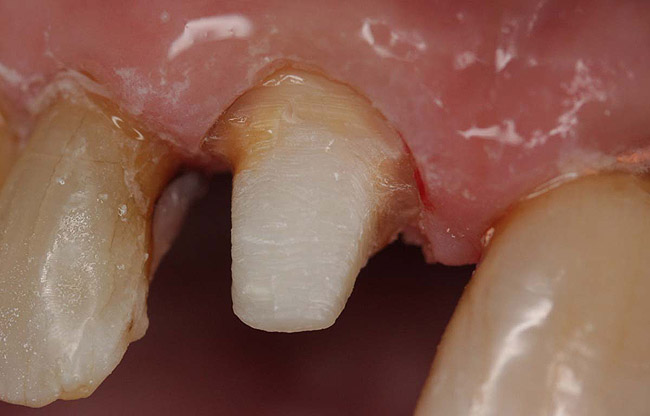

Figure 10  Final tooth preparation to accept a PFM crown.

Figure 10

Figure 11  Final porcelain-fused-to-metal crown.

Figure 11

A Class IIIN maxillary left second molar required restoration (Figure 6). Four canals, a chamber space, and little cross section of tooth structure were in the gingival third. Gutta-percha was removed with a Peeso reamer supplied in the C-1 kit. The canal was shaped with a bur in the kit, which was the same size as the corresponding post (Figure 7). The tooth structure was bonded with Brush & Bond™ (Parkell, www.parkell.com), and then the resin cement was spun into the canal with a lenticulo spiral. A C-1 white post was placed in the palatal canals (Figure 8). The C-1 White Post is a fiber-reinforced composite post, which flexes at the same rate as dentin to minimize root stresses.

Core build-up was completed with Absolute Dentin™ (Parkell, www.parkell.com) dual-cure high-strength core composite. There are variations on color and how materials cure. For example, Light-Core™ (Bisco, www.bisco.com) is a light-cured blue material, Encore® (Centrix, www.centrixdental.com) is a self-cure white material, and Para Core (Coltène Whaledent, www.coltene.com) is a dual-cure white or dentin-colored material. Material was placed directly and light-cured for 40 seconds (Figure 9). Final preparation for a PFM was completed (Figure 10). The final crown was placed (Figure 11).